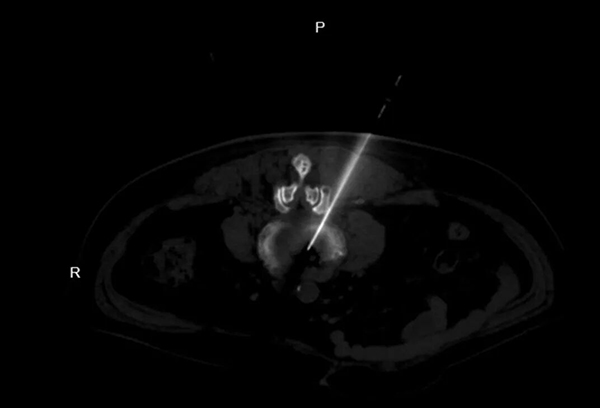

首先,我们把椎间盘比作一个充满果冻的轮胎。当“轮胎”破裂,“果冻”突出压迫神经,就会引发疼痛。而臭氧溶盘术在高清影像引导下,将一根仅1毫米的穿刺针精准送达突出部位,通过氧化、抗炎、消融三重作用,快速减轻神经压迫,修复受损组织,被誉为“绿色疗法”。

2.精准高效,安全性高:在C型臂或CT实时引导下操作,直达病灶,不伤及正常组织,对脊柱稳定性无影响。